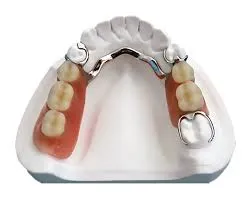

The Expansion Screw is an essential component used in orthodontic appliances to gradually expand the palate and create additional space for proper tooth alignment. It is commonly used in removable orthodontic plates and other dental appliances that require controlled expansion.

Manufactured with high-quality stainless steel, this expansion screw ensures durability, precision, and smooth activation during treatment. Its compact design allows easy integration into acrylic plates while maintaining patient comfort.

Orthodontists and dental technicians rely on this component for effective treatment planning and predictable results. The screw mechanism allows gradual expansion by periodic activation, helping achieve proper dental arch development.